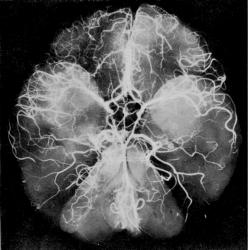

Ниже иллюстраций «по случаю» представлены схемы из монографии Д. Лужа. Рентгеновская анатомия сосудистой системы. Будапешт, 1973.